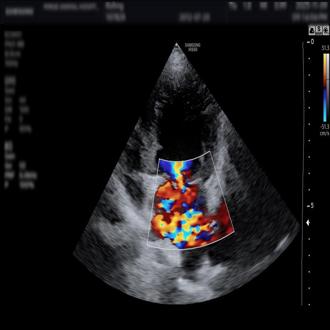

심부전

심부전은 초기에는 기침이나 숨이 차 보이는 증상처럼 일상적인 변화로 시작되는 경우가 많습니다. 하지만 진행될 경우 호흡 곤란과 활동성 저하로 생활의 질에 큰 영향을 미칠 수 있습니다.

심장 기능과 폐 상태를 종합적으로 평가한 뒤 약물 조절과 생활 관리, 보호자가 주의해야 할 신호까지 함께 안내해 아이의 일상이 무너지지 않도록 관리합니다.